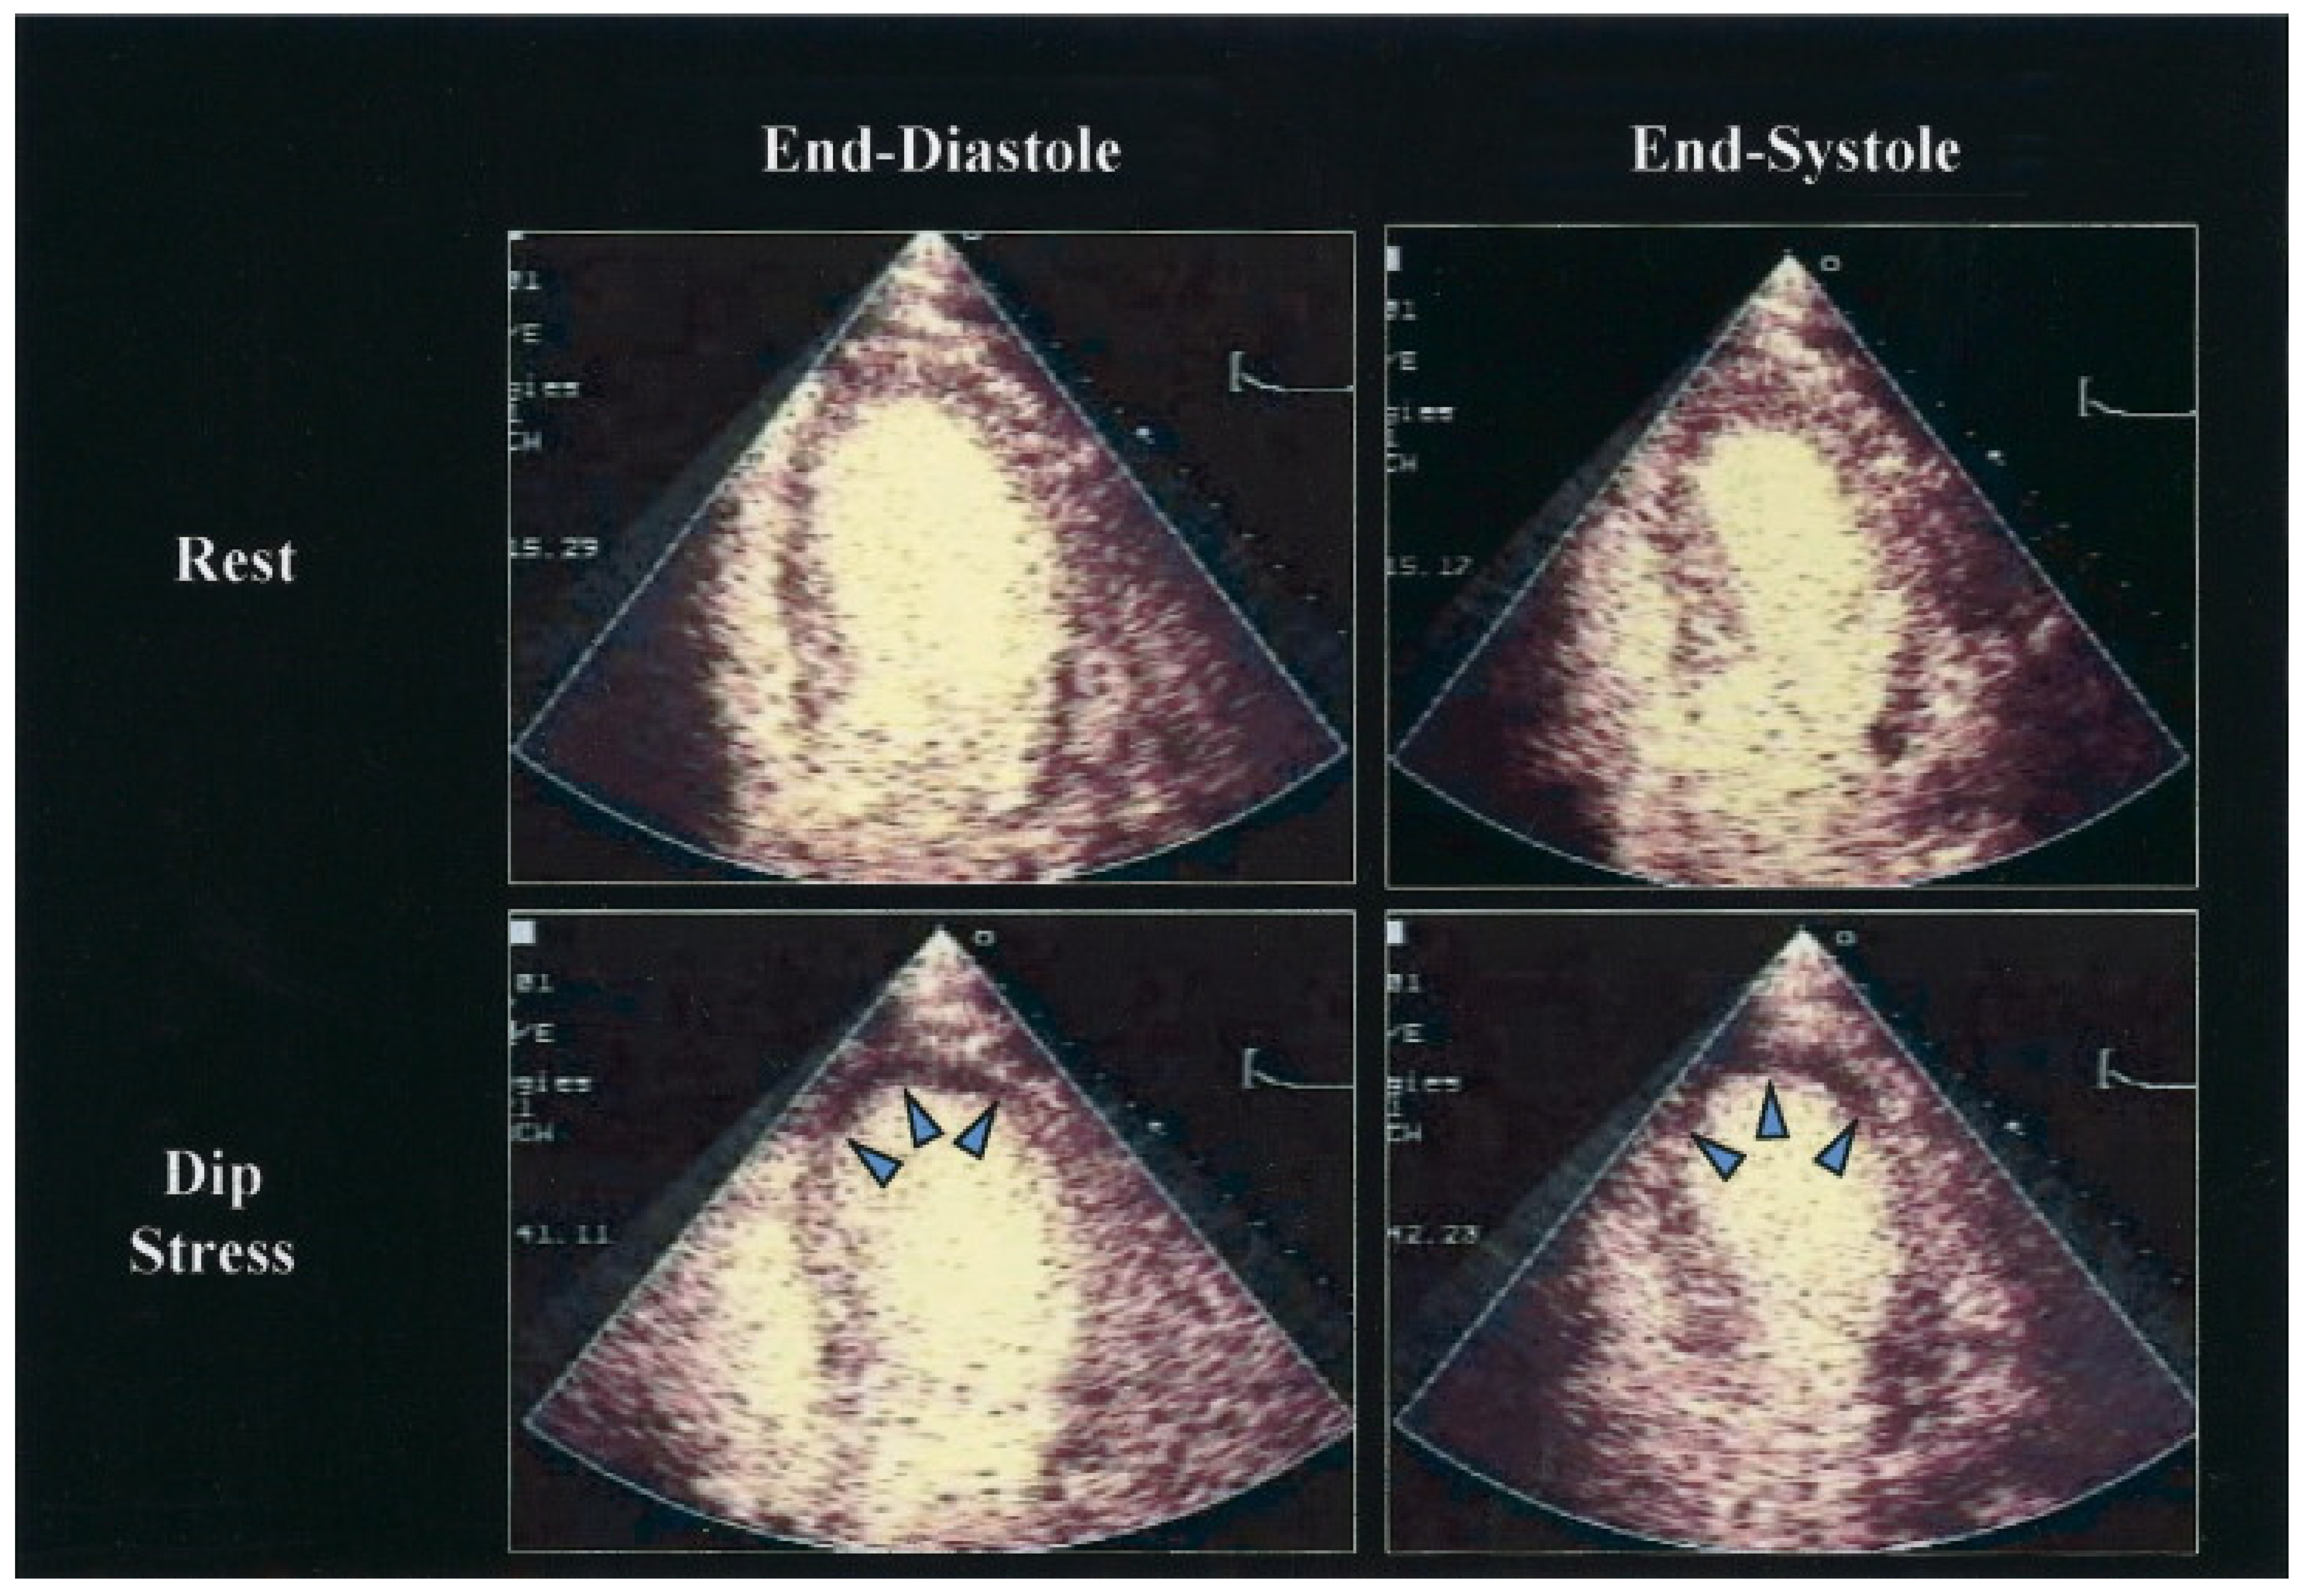

Figure 4.

Dipyridamole (Dip) stress contrasts echocardiography using real-time perfusion imaging at a low mechanical index, showing images at end diastole and end systole in a patient with significant stenosis of the left anterior descending coronary artery. Note the perfusion defect that developed in the apex (highlighted by arrows) and the corresponding wall motion abnormality. Reprinted from Journal of the American College of Cardiology, Volume 45, Issue 11, Armstrong, W.F. et al. [122], Stress Echocardiography: Current Methodology and Clinical Applications, pages 1739–1747, Copyright 2005, with permission from Elsevier.